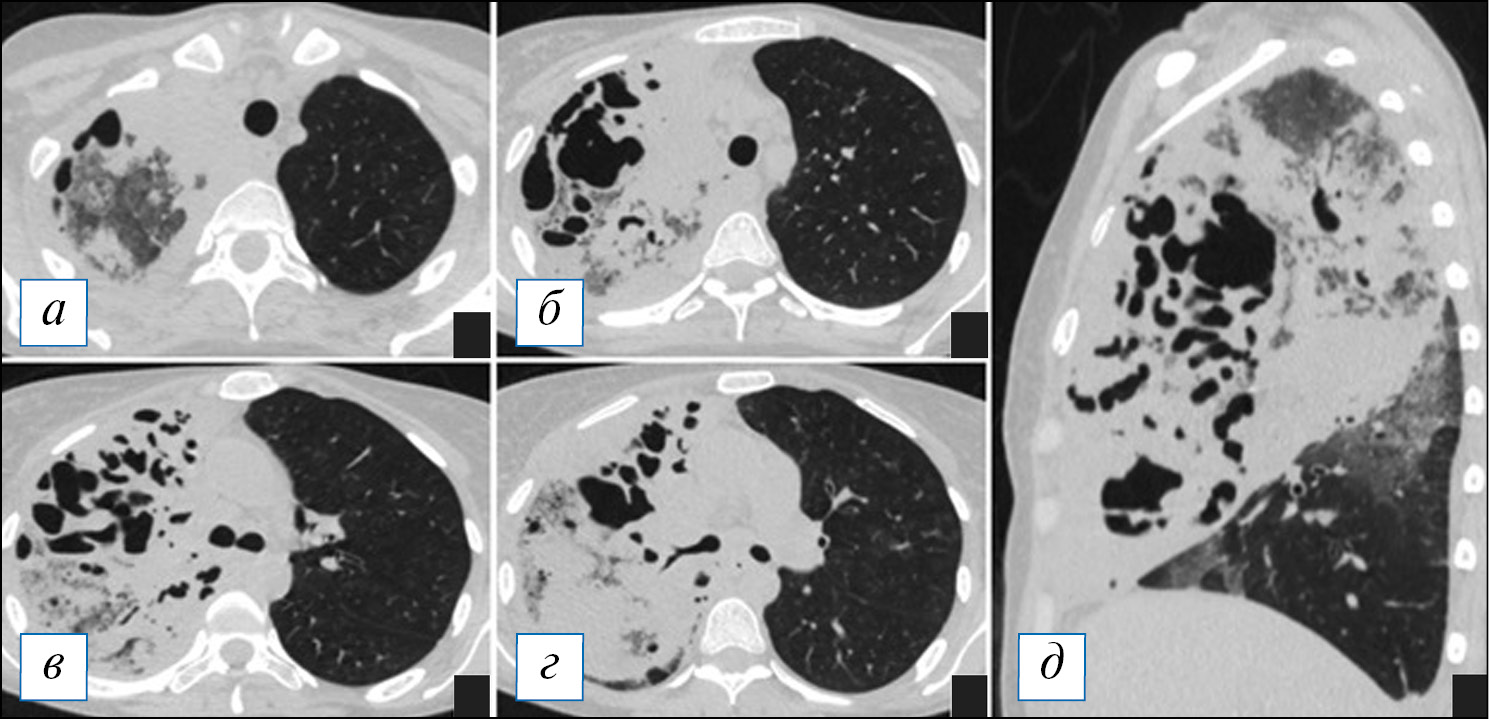

На КТ органов грудной клетки воспалительная инфильтрация легочной ткани при гангрене легкого не имеет четких границ и захватывает большое пространство — обычно больше одной доли, нередко все легкое (рис. 14). В начале процесса на КТ гангрена проявляется обширным участком консолидации (где частично прослеживаются просветы бронхов) или сочетанием консолидации с «матовым стеклом» (рис. 15). Далее, в динамике, на этом фоне появляются в большом количестве полости, обычно малого и среднего размера, в просвете которых обнаруживаются отдельно лежащие фрагменты легкого — секвестры (аваскулярные при контрастировании); могут быть видны сосудистые балки в виде тяжей, которые некротизируются обычно в последнюю очередь (рис. 16).

Рис. 14. Компьютерная томография органов грудной клетки в аксиальной (а–г) и сагиттальной (д) проекциях. Гангрена верхней доли левого легкого. Имеется тотальная инфильтрация верхней доли с наличием множественных полостей распада неправильной формы, а также фокусы инфильтрации в иных отделах легких. Небольшой выпот слева. [Изображения из архива авторов]. / Fig. 14. Axial (а–г) and sagittal (д) chest CT images. Gangrene of the upper lobe of the left lung. There is a total infiltration of the upper lobe with the presence of multiple irregular-shaped destructive cavities, as well as little areas of infiltration in other parts of the lungs. A small pleural effusion is seen on the left. [Images from the authors’ archive].

Рис. 15. Компьютерная томография органов грудной клетки в аксиальной (а–г) и сагиттальной (д) проекциях. Гангрена верхней и средней доли правого легкого в начальной стадии. Наблюдается тотальная инфильтрация долей в виде «матового стекла» и консолидации, на фоне которой имеются полости причудливой формы, склонные к слиянию. [Изображения из архива авторов]. / Fig. 15. Axial (а–г) and sagittal (д) chest CT images. Gangrene of the upper and middle lobes of the right lung at its initial stage. There is a total infiltration of the lobes in the form of ground glass opacity and consolidation, against which there are oddly shaped cavities that tend to merge. [Images from the authors’ archive].

Рис. 16. Компьютерная томография органов грудной клетки в аксиальной проекции от 14.09.2020 (а, б) и 22.09.2020 (в, г). Отрицательная динамика гангрены легкого. Наблюдается слияние мелких полостей в более крупные, неправильной формы; содержимое в полостях отсутствует. [Изображения из архива авторов]. / Fig. 16. Chest CT, axial projection from 14.09.2020 (а, б) and 22.09.2020 (в, г). Negative dynamics of lung gangrene. Small cavities confluence into larger ones, irregular shapes, the contents in the cavities are absent. [Images from the authors’ archive].

В полостях имеется гной, который визуализируется в виде участков жидкости с горизонтальным уровнем (лучше различим от ткани легкого при контрастном усилении). В подавляющем большинстве случаев гангрена легкого сочетается с плевральным выпотом и эмпиемой при расплавлении стенок полостей и висцерального плеврального листка. Переход выпота в эмпиему можно определить по появлению газовых пузырьков на фоне жидкости, более крупного скопления газа в плевре с горизонтальной границей раздела сред, неоднородности жидкостного содержимого. При контрастном усилении плевра обычно утолщена, накапливает контрастный препарат. В тяжелых случаях секвестрированные участки легкого могут попадать в плевральную полость.